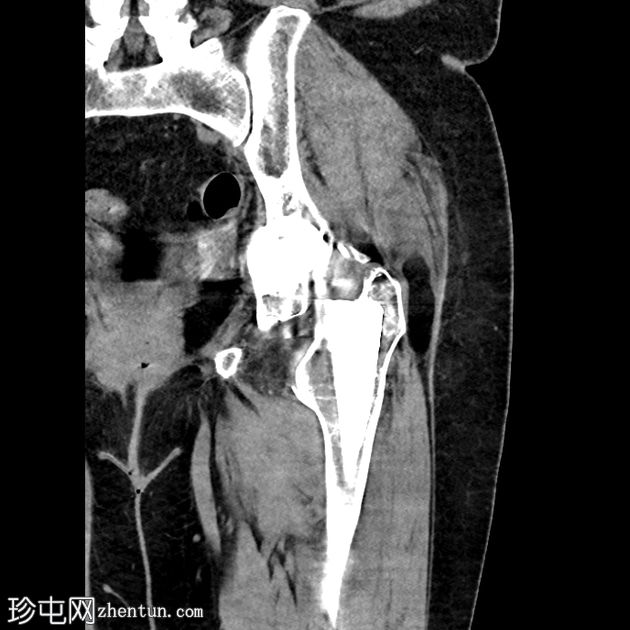

骨盆及左髋关节

X线片

1.png

正位片

双侧全髋关节置换术假体完整,无松动迹象。

左侧股骨大转子下区外侧皮质中断,侧位片显示最佳,提示假体周围骨折。